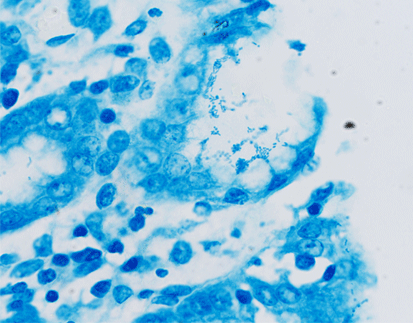

SPECIAL STAINS